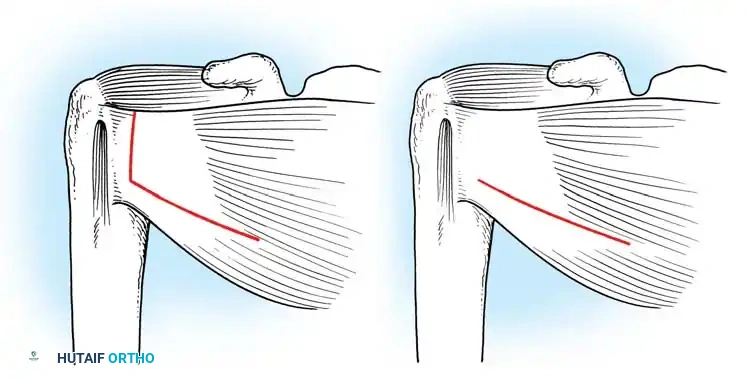

A vertical or T-shaped capsulotomy is performed based on the degree of capsular laxity and the planned shift.

- For a standard Bankart repair with an inferior capsular shift, a vertical incision is made 1 cm medial to the humeral articular margin. A horizontal limb can be added to create superior and inferior capsular flaps.

- Tagging sutures are placed in the capsular flaps for traction.

Capsular Shift and Closure

To address capsular redundancy, an inferior capsular shift is performed.

- The arm is positioned in 30 to 45 degrees of abduction and 20 degrees of external rotation.

- The inferior capsular flap is advanced superiorly and laterally, tensioning the IGHL complex. The sutures from the anchors are passed through the shifted capsule and tied.

- The superior flap is then brought down over the inferior flap in a "pants-over-vest" fashion to reinforce the anterior wall and close the rotator interval.